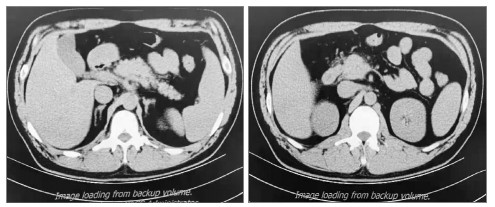

如图 2、图 3示:行血浆置换及CRRT治疗后,患者TG水平明显下降,腹痛也随之改善。患者于EICU共治疗4 d后一般情况显著改善,遂转入普通病区治疗。于入院第8日复查腹部CT可见胰周渗出较前吸收(见图 4),次日出院。出院后继续口服非诺贝特,3个月后随访查腹部CT可见患者胰腺体积、形态基本恢复,胰周渗出基本吸收,见图 5。

| 左图为胰尾;右图为胰头 图 4 入院第8日上腹部CT |